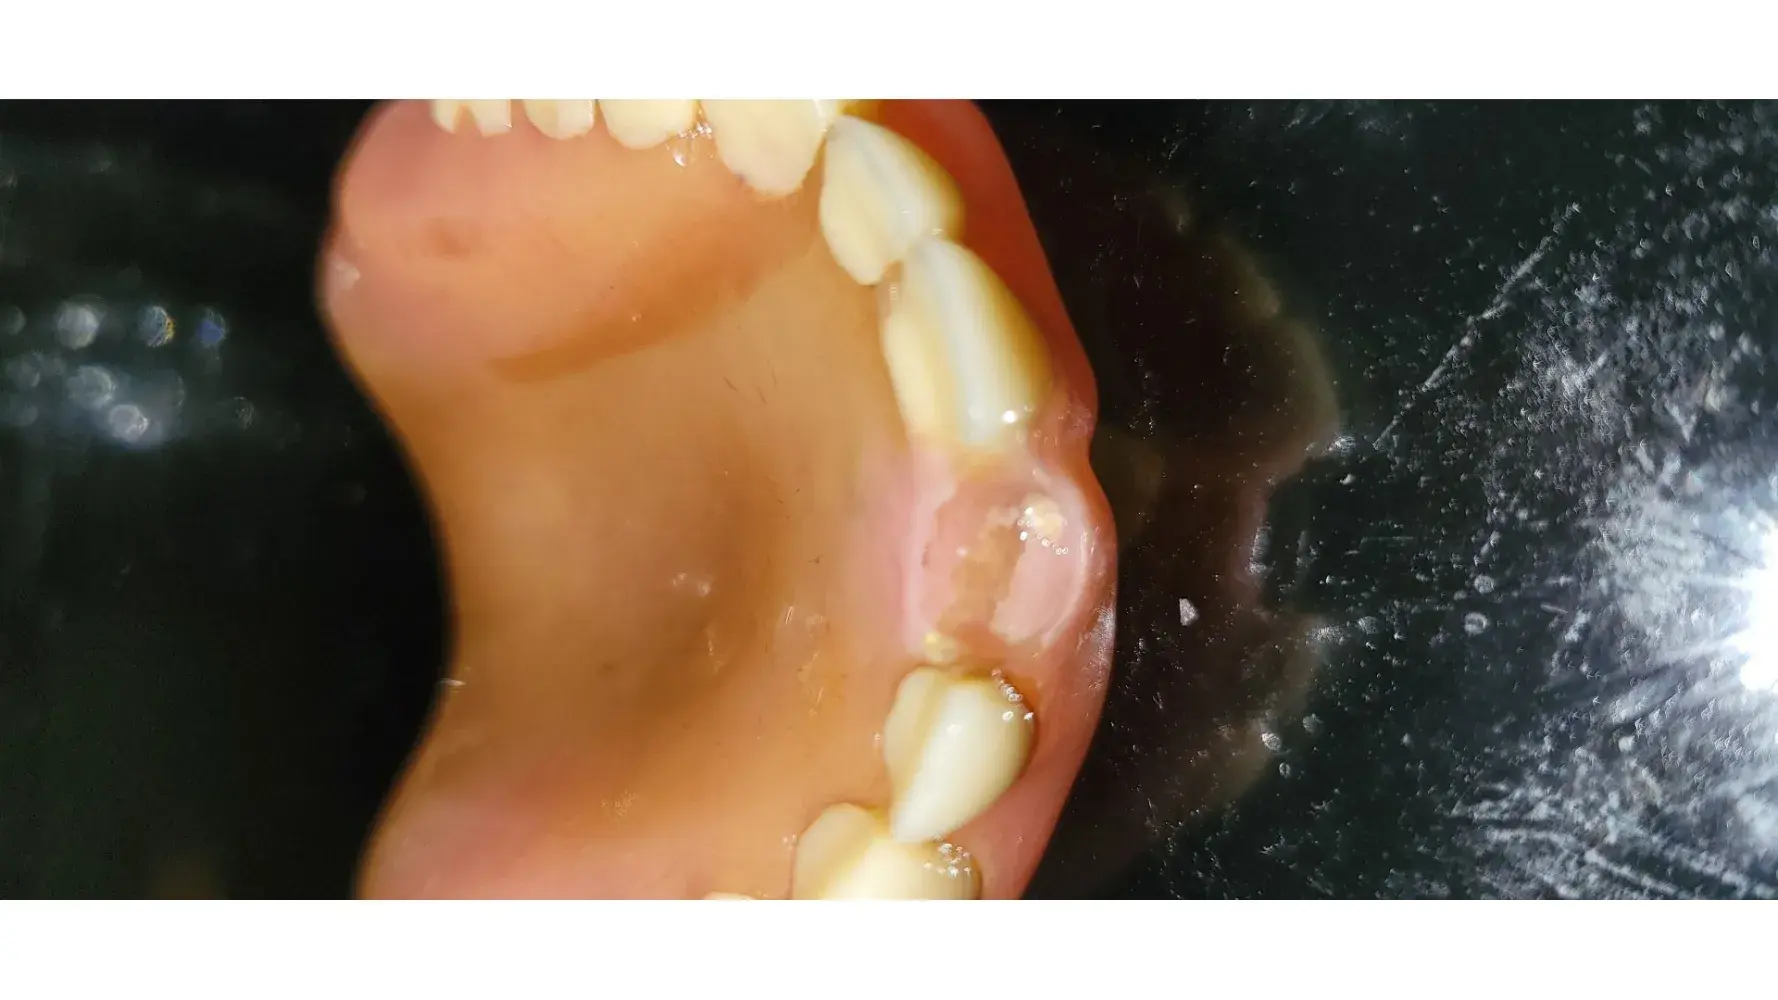

I was cut on my lip, and bleeding, which I didn't discover until I looked in the mirror, they never told me after the procedure. I was also brushed bad on my chin, during a filling. I have since, started going to another dentist, after the horrible service, and many different billinote issues, such as getting billed for amounts, when I still had a balance on my care credit card to cover the balance that was not even used yet. I have had to get two of the teeth done over, that I got a root canal and filing from at aspen, by my new dentist which I love and is much more experienced than the dentist at aspen. I have made several complaints to them as well. I now have a balance of 199.75, and they are mysteriously saying it's really $268, when I has no previous balance